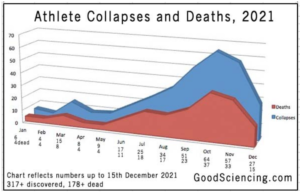

These repeated shots are not only likely to weaken your immune system. They compound the build-up of dangerous spike proteins wreaking havoc in the body. Heart attacks, strokes, clotting… we’ve been documenting the fallout from the toxic spikes for nearly a year.

Are the boosters more deadly than Omicron?

What is the risk/benefit of vaxxing for Omicron? Comparing deaths from the variant with fatalities from the jab is an obvious place to start a risk/benefit analysis.

Contrary to Berry’s if you’re not vaxxed it can cause you to die threat, the Omicron virus is not proving fatal. Risk of death from the variant to date is effectively zero. But deaths from the boosters are piling up. Lack of efficacy and even negative vaccine effectiveness pale in significance to potential damage from the shots themselves.

While the mainstream media works overtime to find and hype a single death from the Omicron virus, the millions of injuries and possibly hundreds of thousands of deaths from the experimental injections don’t make the news. Now and then a story that can’t be ignored—like the shots causing myocarditis in young people—is permitted in order to broadcast pharma’s spin assuring the public that it is “rare” and “mild”, two of Berry’s favorite terms to dismiss tragic outcomes.